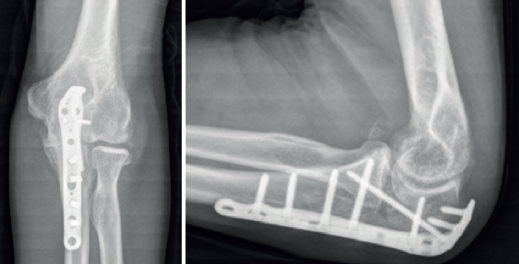

Las placas colocadas en la superficie posterior del cúbito son el sistema de fijación recomendado, proporcionando una fijación más resistente que los cerclajes con agujas de Kirschner y además permiten la fijación adicional de los fragmentos óseos y de la coronoides con tornillos o placas ortogonales en las superficies medial o lateral en los casos con gran conminución metafisaria(1,2,17). Las placas especialmente diseñadas de olécranon (Figuras 5 y 6) o las placas de compresión dinámica de contacto limitado (LC-DCP) de 3,5 mm conformadas para adaptarse a la morfología del cúbito son preferibles a las placas semitubulares, al aportar una fijación más estable(2,18,19).

Cuando la fractura del olécranon incluye una fractura de la coronoides, la reducción y la fijación de esta es condición imperativa para conseguir la estabilidad humerocubital (Figuras 7, 8 y 9). La reducción puede llevarse a cabo a través de la fractura del olécranon o por medio de un abordaje medial, separando o a través de la musculatura flexora/pronadora, teniendo identificados y protegidos el nervio cubital y el fascículo anterior del ligamento colateral medial. En los casos en los que es necesario realizar la sustitución de la cabeza del radio por una prótesis, también es posible el acceso lateral a la fractura de la coronoides. En general, el fragmento permite la fijación con tornillos desde posterior a anterior, a través de la placa posterior o independientes de esta, o en ocasiones desde anterior a posterior. La utilización de placas de 2,7 mm o específicas de coronoides, y técnicas de suturas no reabsorbibles atadas sobre el cúbito proximal o sobre la placa de fijación del cúbito son otras opciones(13,17). Para los grandes defectos óseos o fracturas irreconstruibles de la coronoides, se han descrito injertos óseos de la cresta ilíaca e injertos osteocondrales de la cabeza del radio con resultados impredecibles debido a la osificación heterotópica y a la reabsorción ósea del injerto(20,21).

Las fracturas complejas del cúbito que afectan al olécranon o a la coronoides pueden fijarse de “proximal a distal”(1) o de “distal a proximal”(22) en función de lo que resulte más fácil en cada caso. En la fijación de “proximal a distal”, el fragmento proximal del olécranon se fija temporalmente a la tróclea con una o varias agujas de Kirschner de 1,5 mm y el cúbito se reduce sobre el fragmento de olécranon proximal. La fijación de “distal a proximal” se centra inicialmente en la reducción y la fijación de los fragmentos distales del cúbito con objeto de simplificar los trazos de fractura y finalmente proceder a la reducción y la fijación con el fragmento proximal del olécranon. En la reconstrucción de la escotadura mayor del olécranon, se deben tener en cuenta la relación anatómica normal de la coronoides con el olécranon y la existencia de la zona desprovista de cartílago en la escotadura mayor. La incongruencia articular en las fracturas conminutas tiene menos impacto en el resultado clínico que la falta de alineación, altura y rotación de la escotadura mayor del olécranon(1).